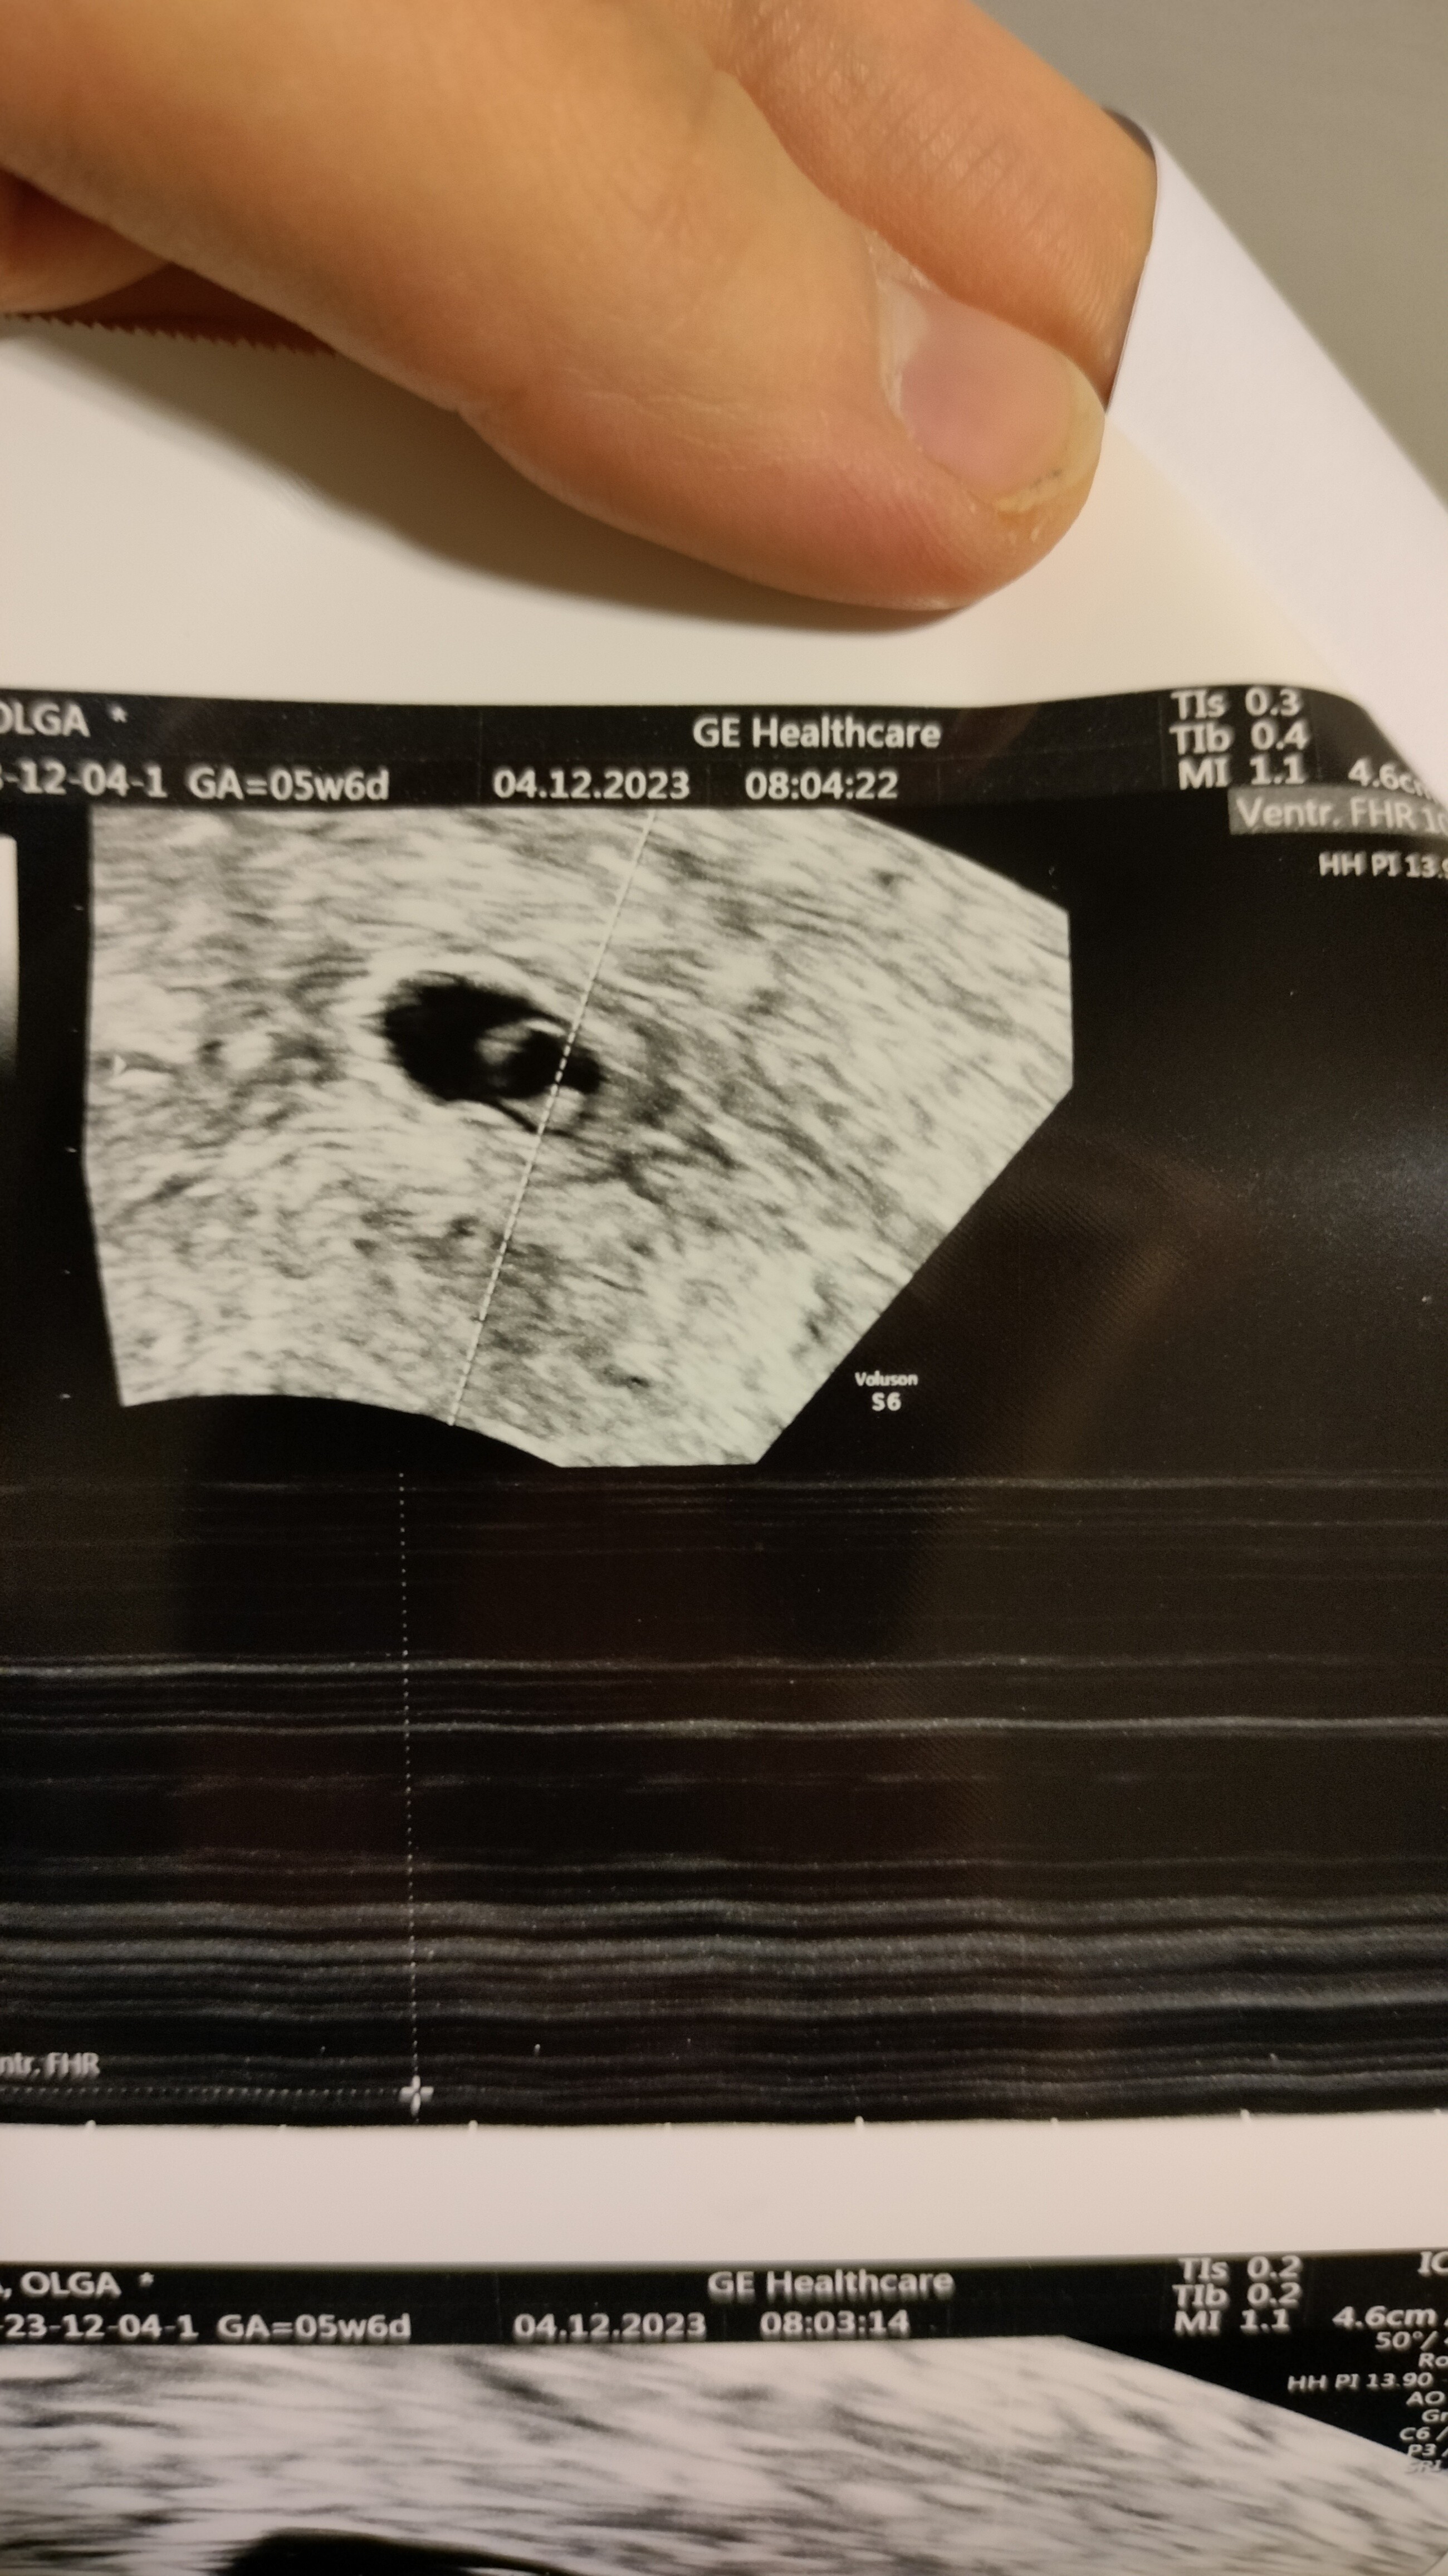

Wracam do Was na chwilę. Jest zarodek z bijącym serduszkiem, lekarka w szoku takim samym jak i ja. Niestety rokowania są kiepskie ze względu na tą betę i tętno bombelka na granicy

• IMG20231204081246.jpg

IMG20231204081246.jpg

1,7 MB · Wyświetleń: 175

Kompletnie nie wiem jak mam się czuć. Totalna pustka w środku. Wolałabym naprawdę żeby mi lekarka powiedziała że już jest po wszystkim, niż jakby się miało okazać że w czwartek już serduszko nie będzie biło